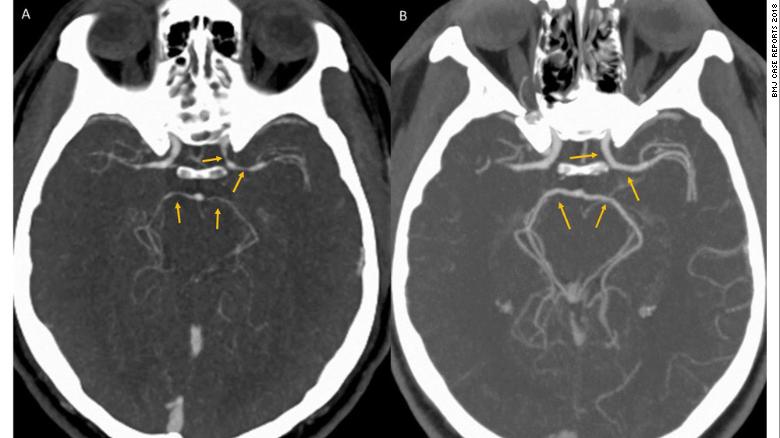

H́nh ảnh chụp CT năo bộ của người đàn ông ở Bệnh viện Henry Ford, Mỹ. (Ảnh: CNN)

Bệnh nhân không có bất cứ sự tổn hại về thần kinh nào hay có triệu chứng của một cơn đột quỵ năo. H́nh ảnh chụp CT cũng loại trừ việc anh này có cục máu đông hoặc bị chảy máu trong năo.

Theo các bác sĩ điều trị, thông qua ảnh chụp CT, họ phát hiện ra một điều lạ lùng: Các động mạch cảnh bên trái và bốn mạch máu khác cung cấp máu cho năo đều bị thu hẹp hơn so với người b́nh thường.

Từ đây, bác sĩ Gunasekaran và các đồng nghiệp đưa ra được kết luận: Bệnh nhân trên đă mắc phải mắc hội chứng co thắt mạch máu co giật hồi phục (hay c̣n gọi là RCVS) do ăn ớt quá cay nóng.